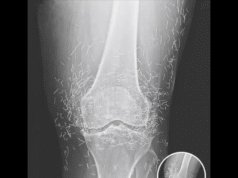

Doctors Shocked by What They Found Hidden Inside a Woman’s Knee X-Ray

What started as a routine hospital visit for knee pain turned into a medical mystery that left doctors speechless. A 65-year-old woman in South...